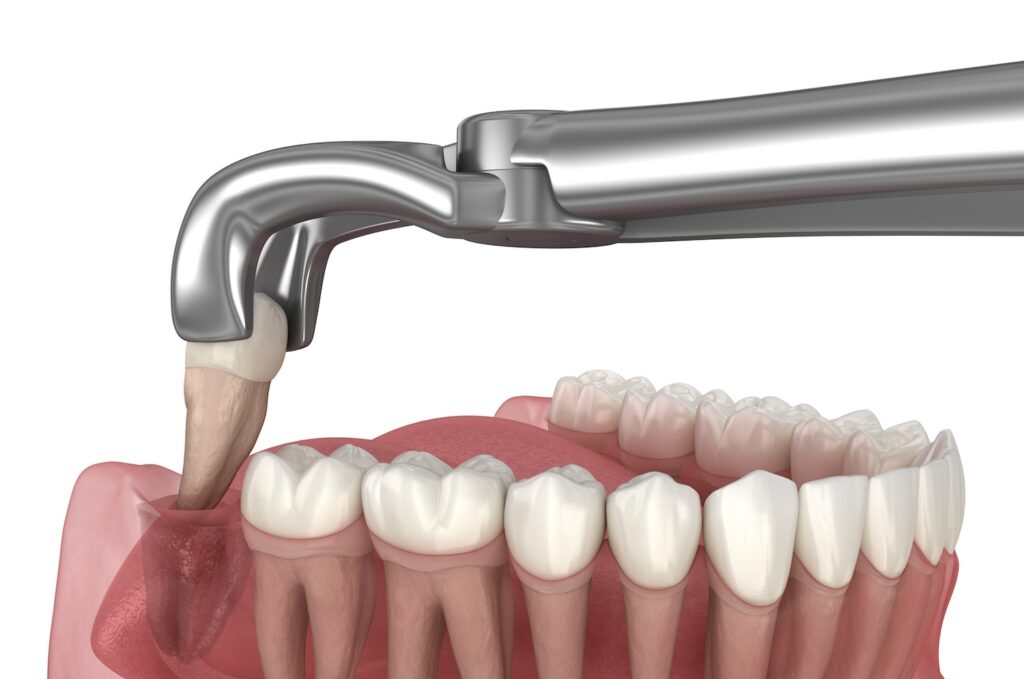

歯を失った際の治療法として一般的にはブリッジ、入れ歯、そしてインプラントが挙げられますが、第4の選択肢としてご自身の歯を移植する「自家歯牙移植」があることをご存知でしょうか??

この方法は親知らずなど、噛み合わせに関与しない歯を用いて、抜歯が必要となる部位に移植をする方法となります。

抜歯の部位に余っている親知らずを移植できるというこの治療法はとても素晴らしい選択肢になるのですが、このコラムではどのような場合に、この自家歯牙移植という治療法を採用できるのかを解説していきます。

上で述べた歯の移植手術の成功の鍵となるのが「歯根膜」になります。

歯根膜とは歯と骨の間を繋ぐ”クッション”のような役目を果たす繊維であり、この歯根膜があることで移植した歯は移植後も再び骨と結びつき、機能を果たすことができます。

つまりこの歯根膜がなければ歯の移植は成功しないということになります。